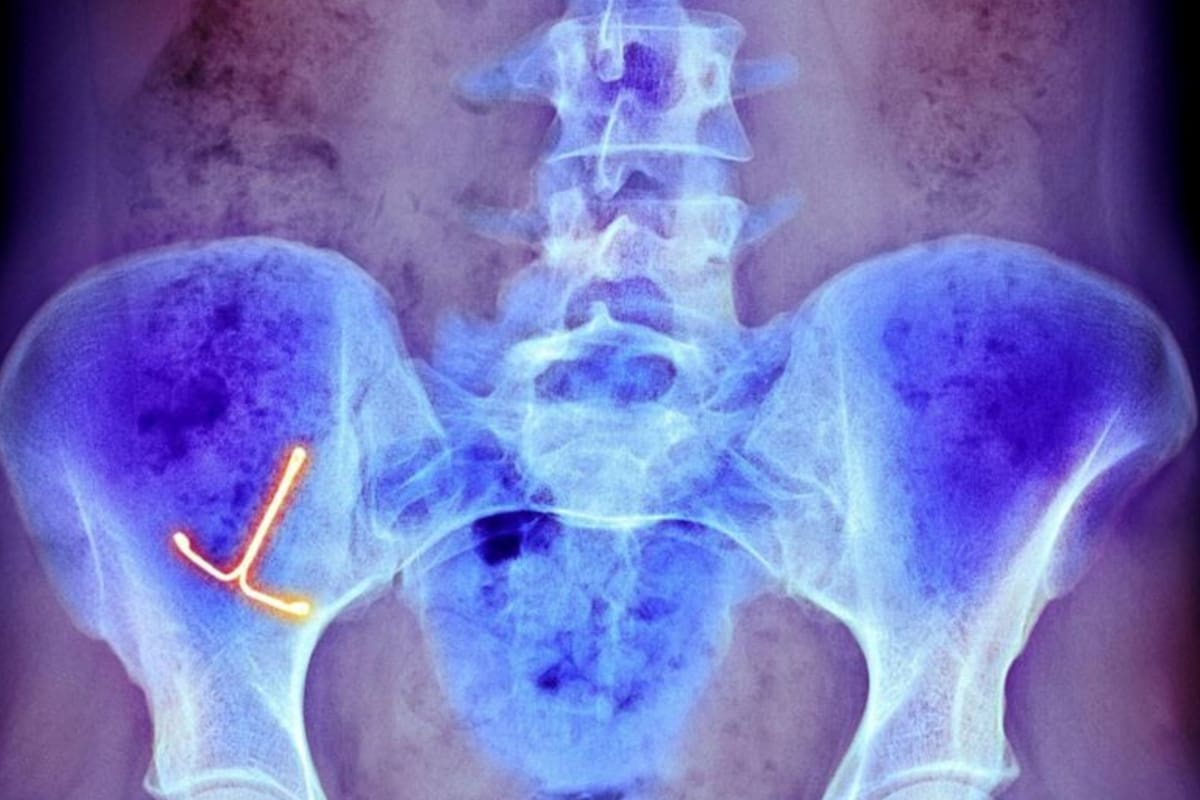

Los cuerpos extraños dentro de la vagina pueden ser aquellos que son médicamente necesarios y aquellos que están allí por otras razones. Los típicos objetos extraños vaginales incluyen pesarios o dispositivos anticonceptivos intrauterinos dañados, que la paciente puede haber olvidado, o que no se haya dado cuenta de que están dañados.

Estos representan riesgos a largo plazo en forma de infecciones, fístulas (una apertura anormal entre un órgano hueco y otro o entre un órgano hueco y la superficie de la piel), y la formación de cálculos.

En este extremo del cuerpo, también se encontraron cosas dentro del ano y el recto. Entre 66% y 85% de los que llegan a urgencias con esa queja son hombres. Uno de los mayores problemas con objetos extraños en el ano o el recto es que se pueden atascar, obstaculizando el movimiento natural de la deposición intestinal. Con el tiempo, esto puede causar un ensanchamiento significativo del tracto con el riesgo de una perforación o ruptura del intestino.